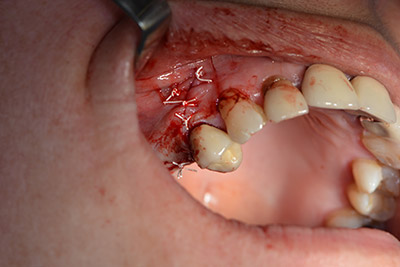

Die klassische Schnittführung (krestal, Entlastung bukkal) und das Präparieren des Mukoperiostlappens erlauben eine gute Übersicht.

Eine resorbierbare Membran bildet die Barriere nach bukkal und deckt das Augmentat ab. Zum Schluss wird speicheldicht vernäht. (Abb. 15 bis 19).